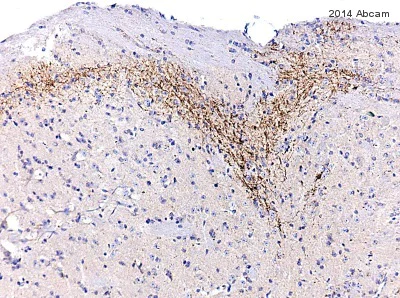

Immunohistochemistry (Formalin/PFA-fixed paraffin-embedded sections) - Anti-Substance P antibody [SP-DE4-21] (AB14184)

• IHC-P

Unknown

Substance P staining at 1 : 1000 of the substancia gelatinosa (dorsal horn) of the guinea pig spinal cord using an HRP-conjugated secondary antibody and DAB.